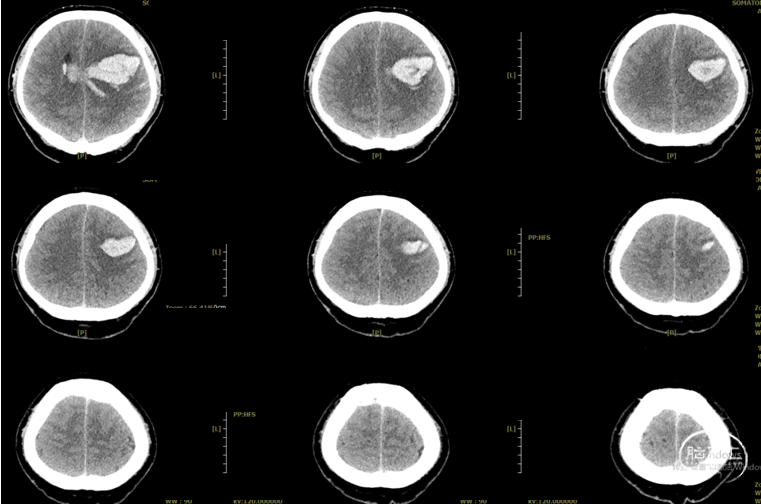

2026.3.15:

2026.3.26: